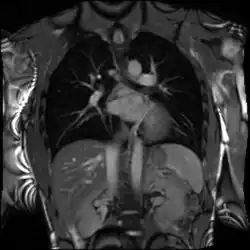

Cardiac magnetic resonance imaging (cardiac MRI, CMR), also known as cardiovascular MRI, is a magnetic resonance imaging (MRI) technology used for non-invasive assessment of the function and structure of the cardiovascular system.[2] Conditions in which it is performed include congenital heart disease, cardiomyopathies and valvular heart disease, diseases of the aorta such as dissection, aneurysm and coarctation, coronary heart disease. It can also be used to look at pulmonary veins.[3]

Cardiovascular MRI is complementary to other imaging techniques, such as echocardiography, cardiac CT, and nuclear medicine. The technique has a key role in evidence-based diagnosis and treatment of cardiovascular disease.[4] Its applications include assessment of myocardial ischemia and viability, cardiomyopathies, myocarditis, iron overload, vascular diseases, and congenital heart disease.[5] It is the reference standard for the assessment of cardiac structure and function,[6] and is valuable for diagnosis and surgical planning in complex congenital heart disease.[7]

Combined with vasodilator stress, it has a role in detecting and characterizing myocardial ischemia due to disease affecting the epicardial vessels and microvasculature. Late gadolinium enhancement (LGE) and T1 mapping allow infarction and fibrosis to be identified for characterizing cardiomyopathy and assessing viability.[8] Magnetic resonance angiography may be performed with or without contrast medium and is used to assess congenital or acquired abnormalities of the coronary arteries and great vessels.[9]